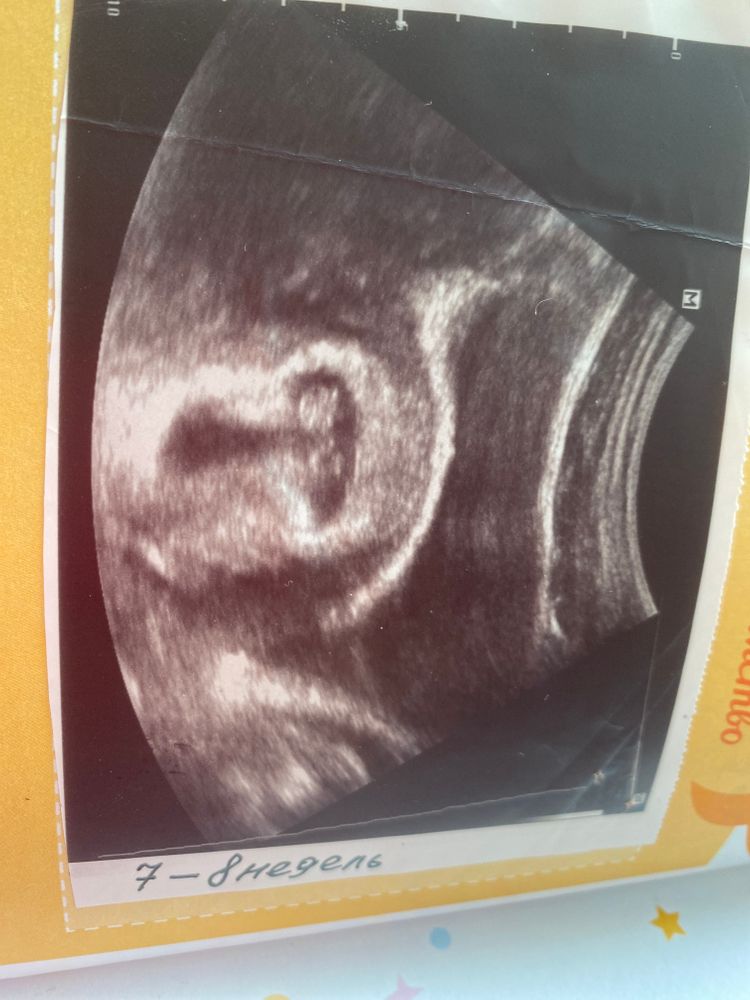

И как я и обещала по методу Рамзи У нас прикрепление слева - девочка